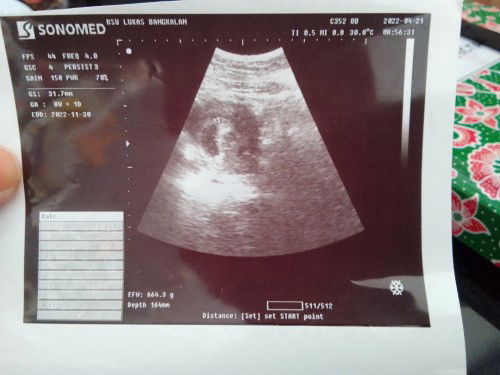

USG 8 minggu

USG pertama kata dokter usia udh 8minggu. Tp janin masih blm tampak . Apa ad yg pernah ngalamin? Atau normalkah?